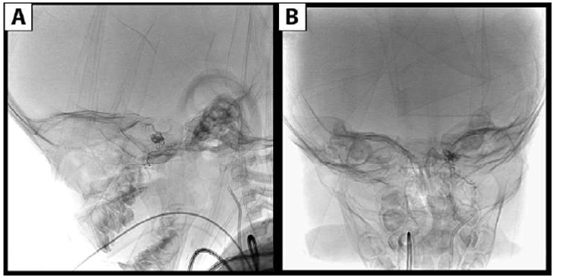

Se decidió realizar tratamiento endovascular mediante embolización con NBCA de las ramas aferentes de carótida externa.Se colocó vaina 4.5 F en arteria femoral derecha y se colocó catéter 4 F en carótida externa izquierda. Mediante sistema coaxial con microateterMagic 1.2 F ymicroguíaMirage 0.008 in.se logra acceder al pedículo principal de carótida externa proveniente de la arteria maxilar interna y se realiza embolizacióncon NBCA al 25% que llega a pie de vena logrando la oclusión del pedículo. El pedículo carótido hipofisario mide menos de 2 mm y no permite su cateterización supraselectiva, se decide nointentar tratarlo ya que se disminuyó notoriamente el flujo de la fistula y que en este momento creemos son mayores los riesgos que los beneficios de intentar embolizar dicho ramo. En los controles angiográficosse observa disminución del flujo y calibre de la vena oftálmica superior. No hubo complicaciones durante el procedimiento (Figura 4,Figura 5yFigura 6).

Figura 4:A)Imagénintra-procedimiento que muestra sistema coaxial con microguía y microcateter, con la punta de este último situada en inicio del ramo fistuloso de maxilar interna. B) Imagen intra-procedimiento en el momento de la inyección de NBCA en ramo fistuloso.

Figura 5:Angiografía digital post-procedimiento con inyección desde carótida externa izquierda que muestra oclusión completa de los ramos fistulosos procedentes de arteria maxilar interna.

Figura 6:Imagen post-procedimiento sin sustracción que muestra el agente embolizante (NBCA) inyectado en las ramas de maxilar interna izquierda. A)perfilB)frente.